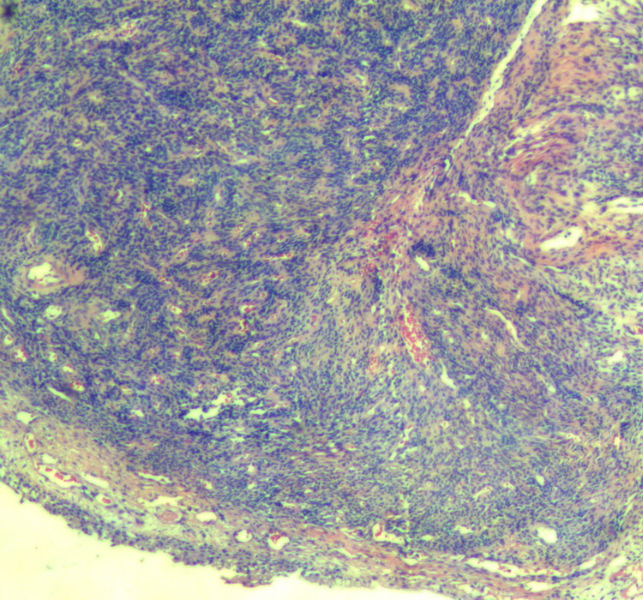

女,67岁,绝经15年。体检发现宫颈绿豆大赘生物。是息肉吗?图1

低分化鳞状细胞癌不能排除

细胞异型性较明显,考虑恶性肿瘤,待免疫组化排外上皮、间叶

不能排除子宫内膜间质肿瘤

不是息肉,像血管源性的肿瘤。

还要做HMB45、Melan-A排除一下Pecoma

片子染色太差了,特像子宫内膜间质的问题,要再看。